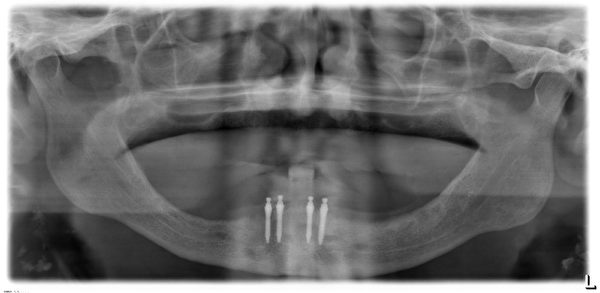

什么是MINI种植体

Mini种植体是一种直径比常规种植体小很多的特殊植体,它是用于活动义齿的修复中,要比传统的义齿修复更加稳定。

Mini种植体允许牙医不用在牙龈上切口直接植入,术后手术痛苦减少,且能够进行即刻修复

目前新加坡有两种植牙技术,一种是迷你植牙,用细小的螺丝来固定牙齿,直径只有约两毫米。

相反的,迷你植牙只需几天,价格是传统植牙的一半。

迷你植牙,它是一种伤口小的微创手术。一些80岁以上的病人,不合适做传统植牙,因为骨头厚度不够,但可利用迷你植牙,帮他们植牙,改变他们的生活。

不过迷你植牙金属较薄,支撑度没有比传统植牙的金属强,长期用力可能破裂。